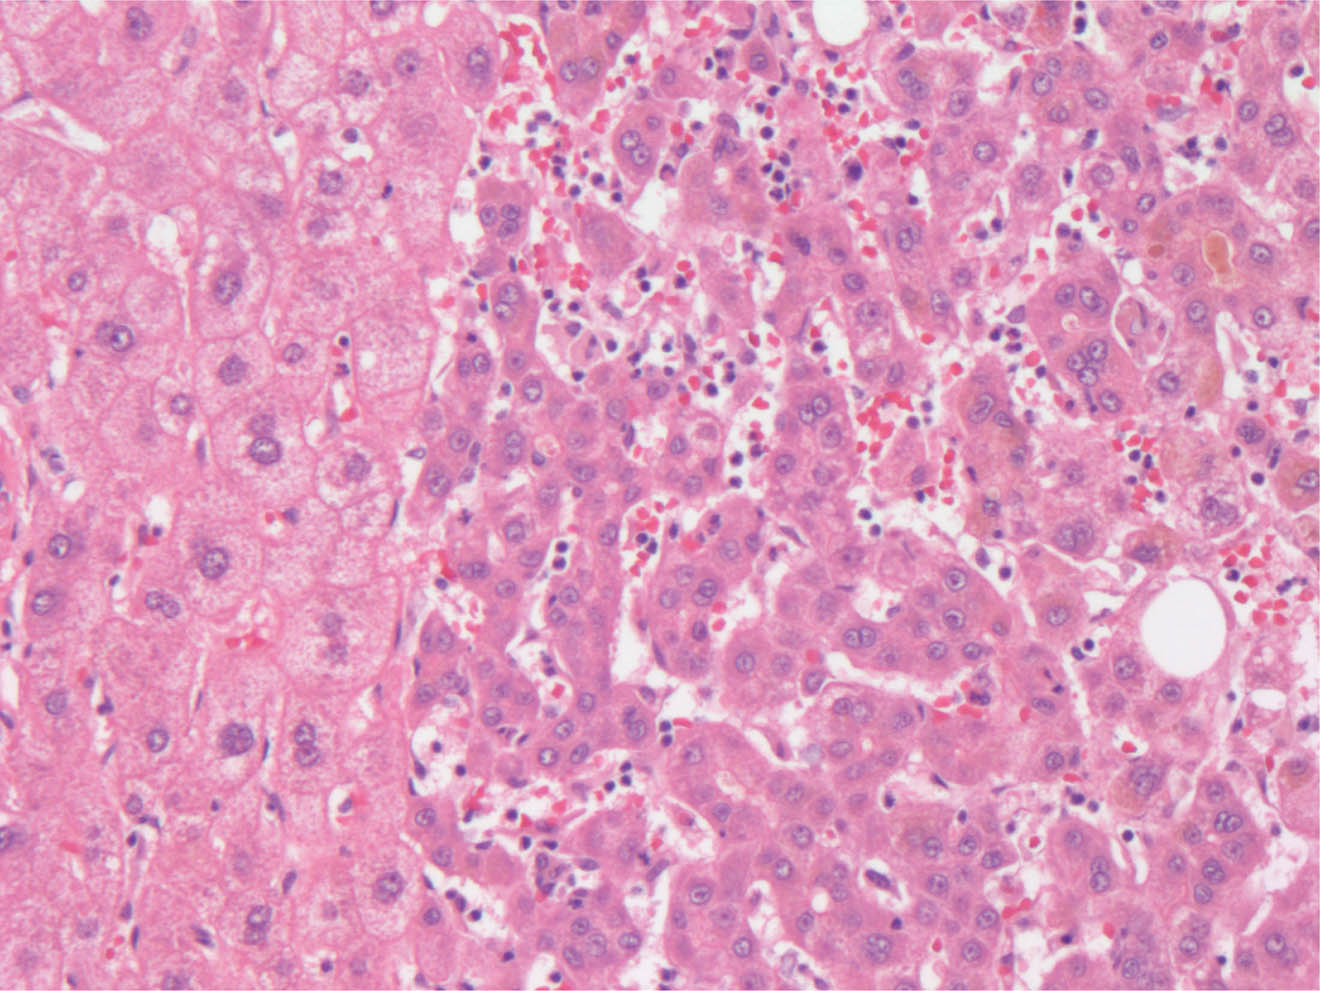

At the cellular level, hepatocellular carcinomas are thought to arise from a dysplastic focus (less than 1 mm) that develops into either a low-grade or a high-grade dysplastic nodule. The high-grade dysplastic nodule, more frequently than the low-grade dysplastic nodule, progresses to hepatocellular carcinoma (24). Since the primordial lesion (dysplastic focus) is less than 1 mm, it is not identifiable by radiologic studies and usually observed in hepatectomy specimens as focal cytological atypia within the hepatocytes. Morphologically, the atypia within the hepatocytes is described as small and large cell changes. The small cell change is characterized by increased nuclear to cytoplasmic ratio, hyperchromasia and cytoplasmic basophilia, giving the impression of crowding. Small change atypia is associated with high-grade dysplastic nodules and a higher risk of developing of hepatocellular carcinoma. The large cell change is characterized by enlarged cells with larger nuclei and cytoplasm, but the nuclear to cytoplasmic ratio is preserved; frequent multinucleation, nuclear polymorphism and hyperchromasia are common. Large cell changes are the predominant alteration in low grade dysplastic nodules and indicate a benign feature (25). The biggest diagnostic challenge is to differentiate a high-grade dysplastic nodule from a well-differentiated hepatocellular carcinoma. Reticulin stain with delineation of the hepatic plates is a reliable ancillary technique in this context. Preservation of the hepatic plate is typical of a high-grade dysplastic nodule, whereas expansion of the hepatic plates is typical of hepatocellular carcinoma. Other morphologic criteria for hepatocellular carcinoma include increased cell nuclei with consequent increased nuclear to cytoplasmic ratio, pseudogland formation and unpaired arteries with absence of portal triads (Figure 1), and sinusoidal capillarization appreciated with CD34 immunohistochemistry and stromal invasion without ductular reaction at the periphery of the nodules (26). The size of the lesion may also be helpful, especially radiologically, with lesions larger than 1 cm and less than 3 cm usually classified as dysplastic nodules, and lesions more than 3 cm as hepatocellular carcinoma (27).

Fig 1

Figure 1. Hematoxylin and Eosin stain 200X. On the left, normal hepatocytes with normal nuclear cytoplasmic ratio as compared to hepatocellular carcinoma (on the right) with increased nuclear cytoplasmic ratio, organized into thick trabeculae and few pesudoglandular structures with bile.